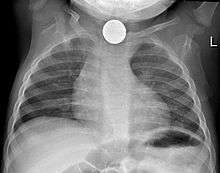

Prior to undertaking endoscopy, attempts should be made to locate the foreign body with x-rays or other non-invasive techniques.[1] For radio-opaque objects, x-rays of the neck, chest and abdomen can be used to locate the foreign body and assist endoscopy.[9] Alternative approaches, including the use of metal detectors, have also been described.[10]

X-rays are also useful for identifying the type of foreign body ingested and complications of foreign body ingestion, including mediastinitis and perforation of the esophagus.[1]